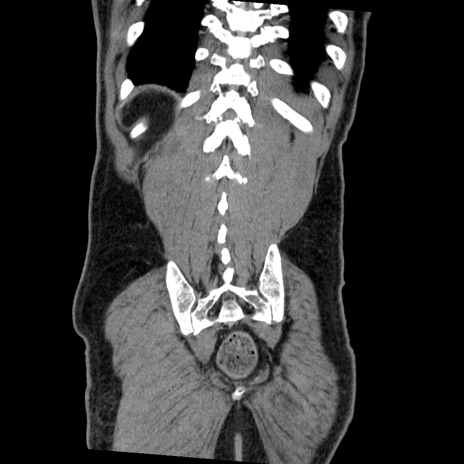

症例22(冠状断像)

【症例】50歳代男性

【主訴】腹痛

【現病歴】AVMからの被殻出血のため回復期リハ病棟入院中。 本日午後3時頃急に下腹部痛が出現した。

【既往歴】AVM、被殻出血、虫垂炎、高血圧

【身体所見】意識晴明、左半身不全麻痺、会話の理解は良好、36.5°C、腹部:膨隆、全体に板状硬、下腹部正中に圧痛点あり、反跳痛-、筋性防御不明、右下腹部にope scar

【データ】WBC 9400、CRP 0.06